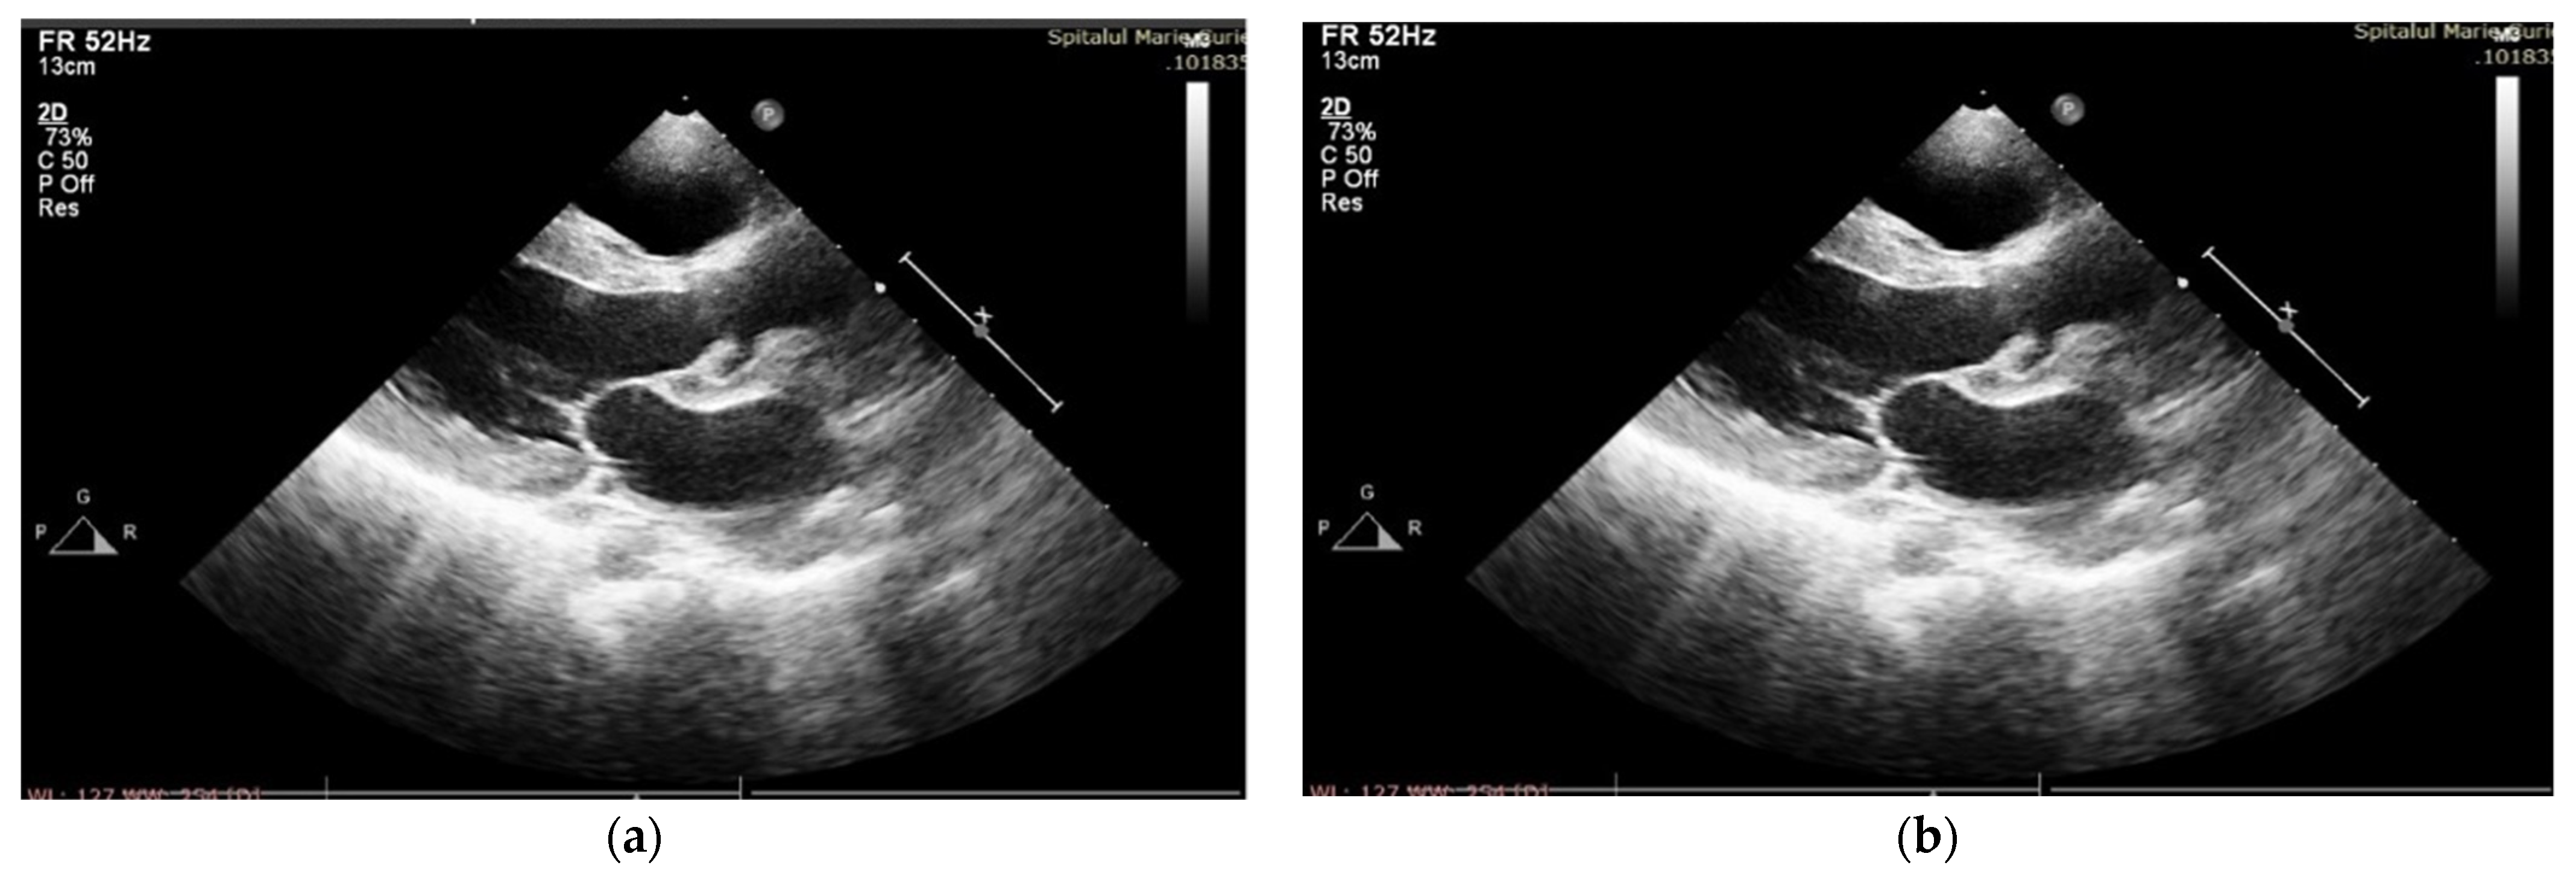

One year after surgery, our patient had a good cardiovascular status with good exercise tolerance and controlled BP on Furosemide and Captopril medication; muscle enzymes were still elevated after surgery (CK = 5156 UI/L, CKMB = 154 UI/L, ALT = 242 UI/L, AST = 147 UI/L, LDH = 649 UI/L), and the athletic deficit was aggravated progressively. The echocardiography showed moderate systolic biventricular dysfunction, with EF = 40%, minor regurgitation of neoaorta, good functionality of pulmonary homograft, mild mitral stenosis and a large residual coarctation (Figure 3).

Figure 3. TTE at one-year follow-up: minor regurgitation of neoaorta.